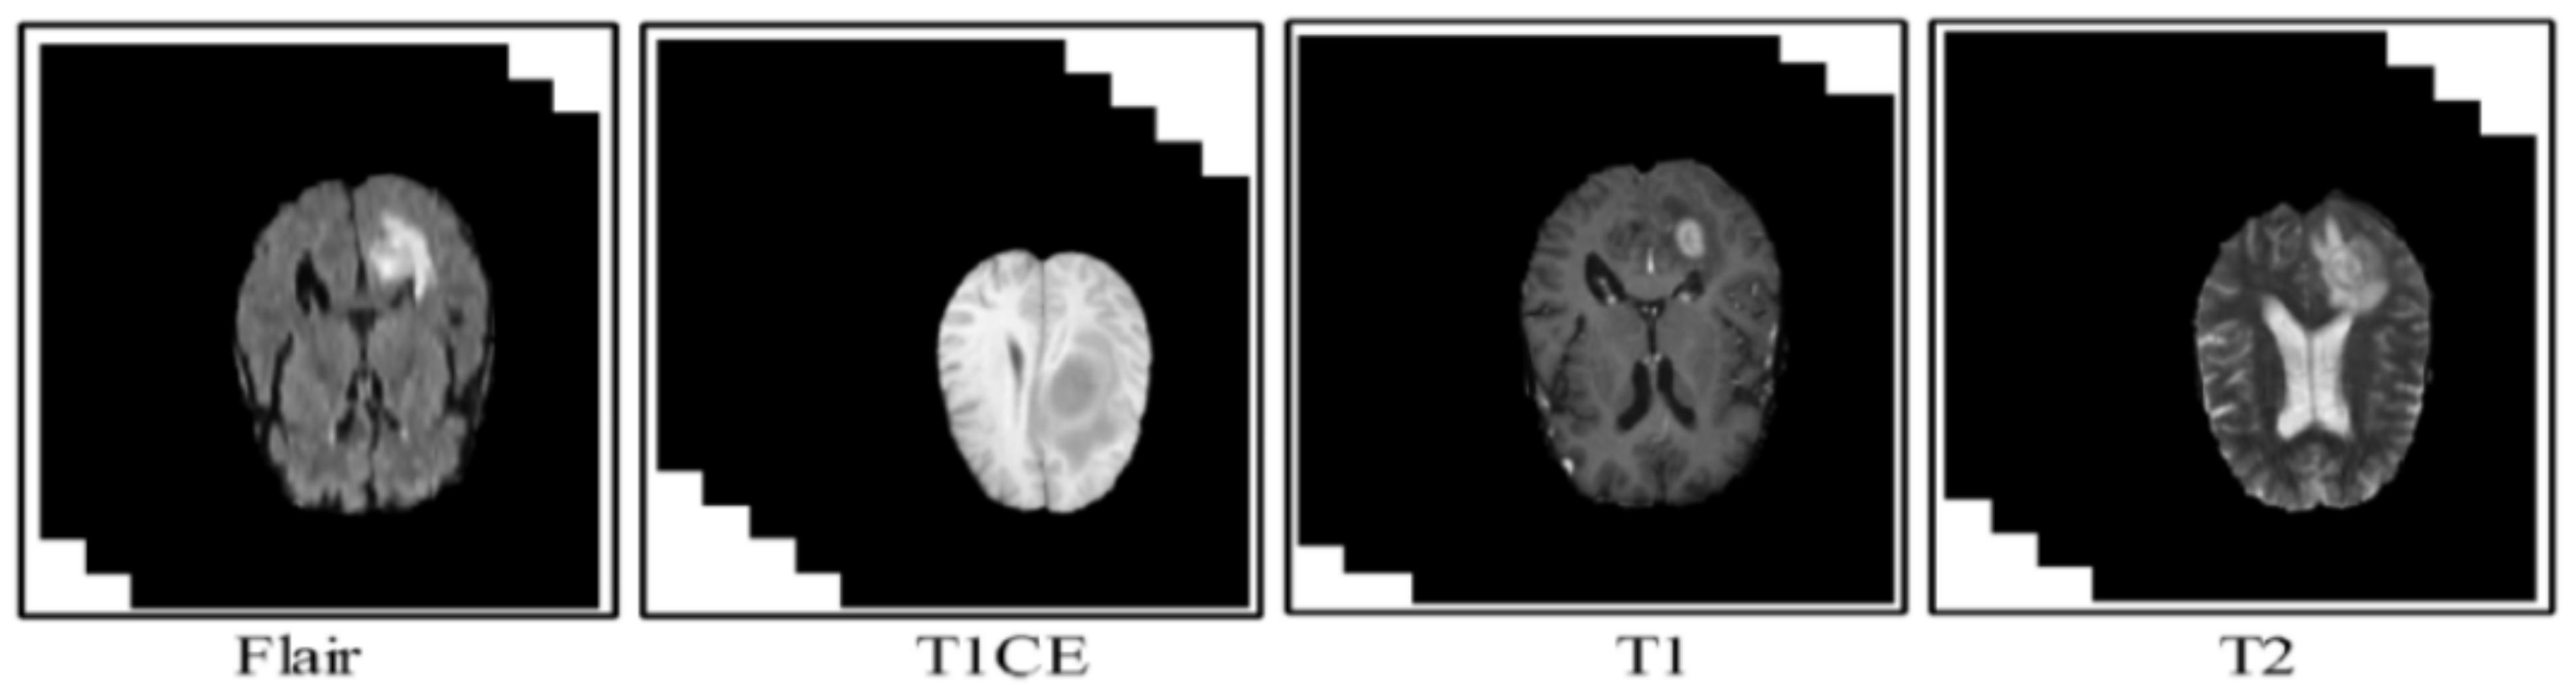

2. Proposed CNN Model in Brain Tumour Dataset